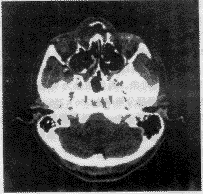

2.2 交互勾边

医生依自身经验勾画出手术中要避开的重要功能区、指定手术路径。图4为其中一个层面上勾画出的眼球、脑干和视神经。图5为图4中区域边界的采样点。手术中心和手术起点的指定在其他层面上,此处不再显示。

图 4 其中一层面上勾画的区域

图 5 对图4区域边界的采样

2.3 求取代价

判断手术路径与勾画的重要功能区的位置关系,根据所赋代价值,计算出手术路径的风险,并显示穿越的区域,图6为其中一条手术路径的判断结果,提示医生该路径穿越了重要功能区,该方案不合适,需要重新指定手术路径。

图 6 一条手术路径的判断结果